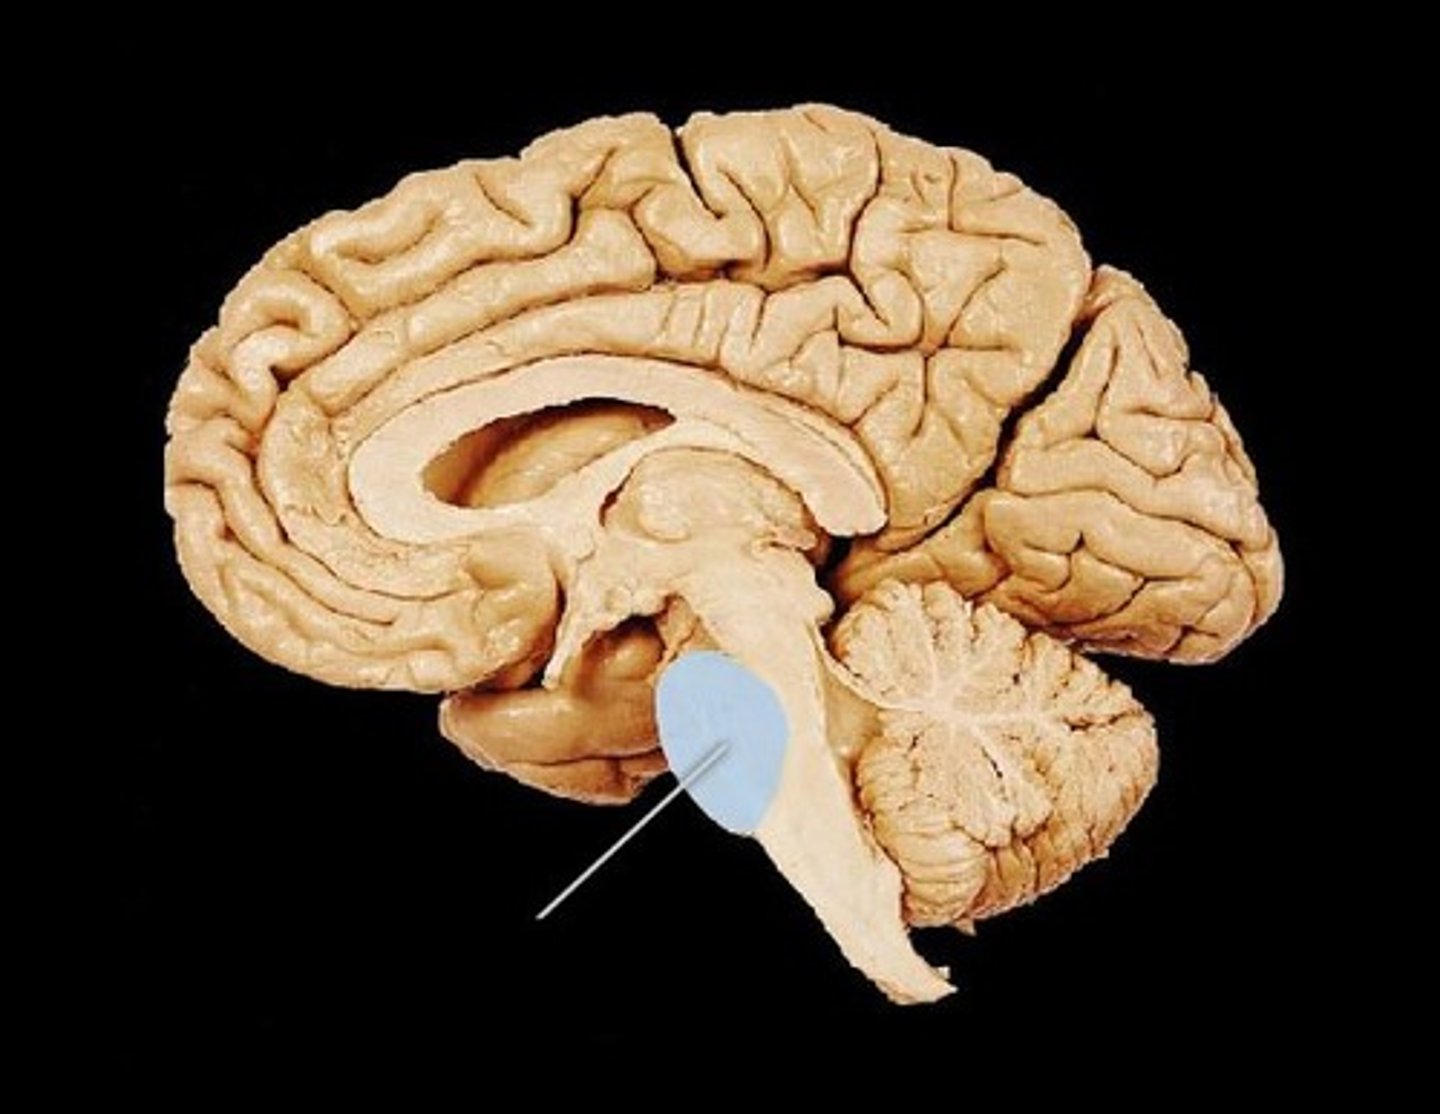

pons

Fourth Ventricle

Thalamus

Hypothalamus

Cerebral Aqueduct

Medulla Oblongata